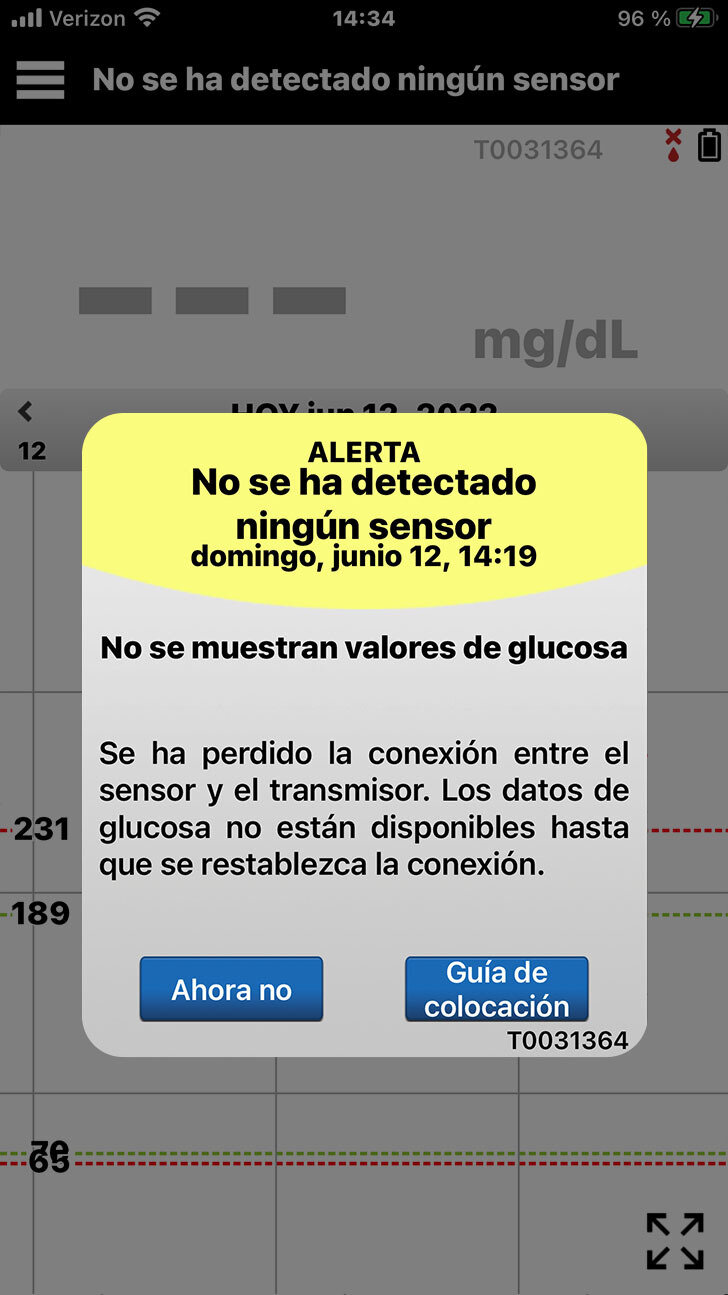

Cuando empiece a programar su configuración personalizada en la aplicación para móvil,

es posible que aparezca un mensaje emergente de alerta No se ha detectado ningún sensor. Solo tiene que tocar Ahora no.

Las Alertas y las Notificaciones se tratarán en los capítulos del Día 2 y Día 3.